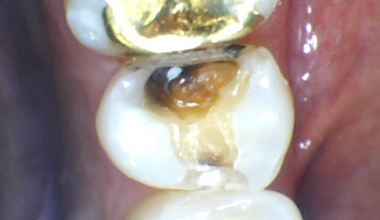

CASE 02

치료 전 -

치료 중 -

치료 후